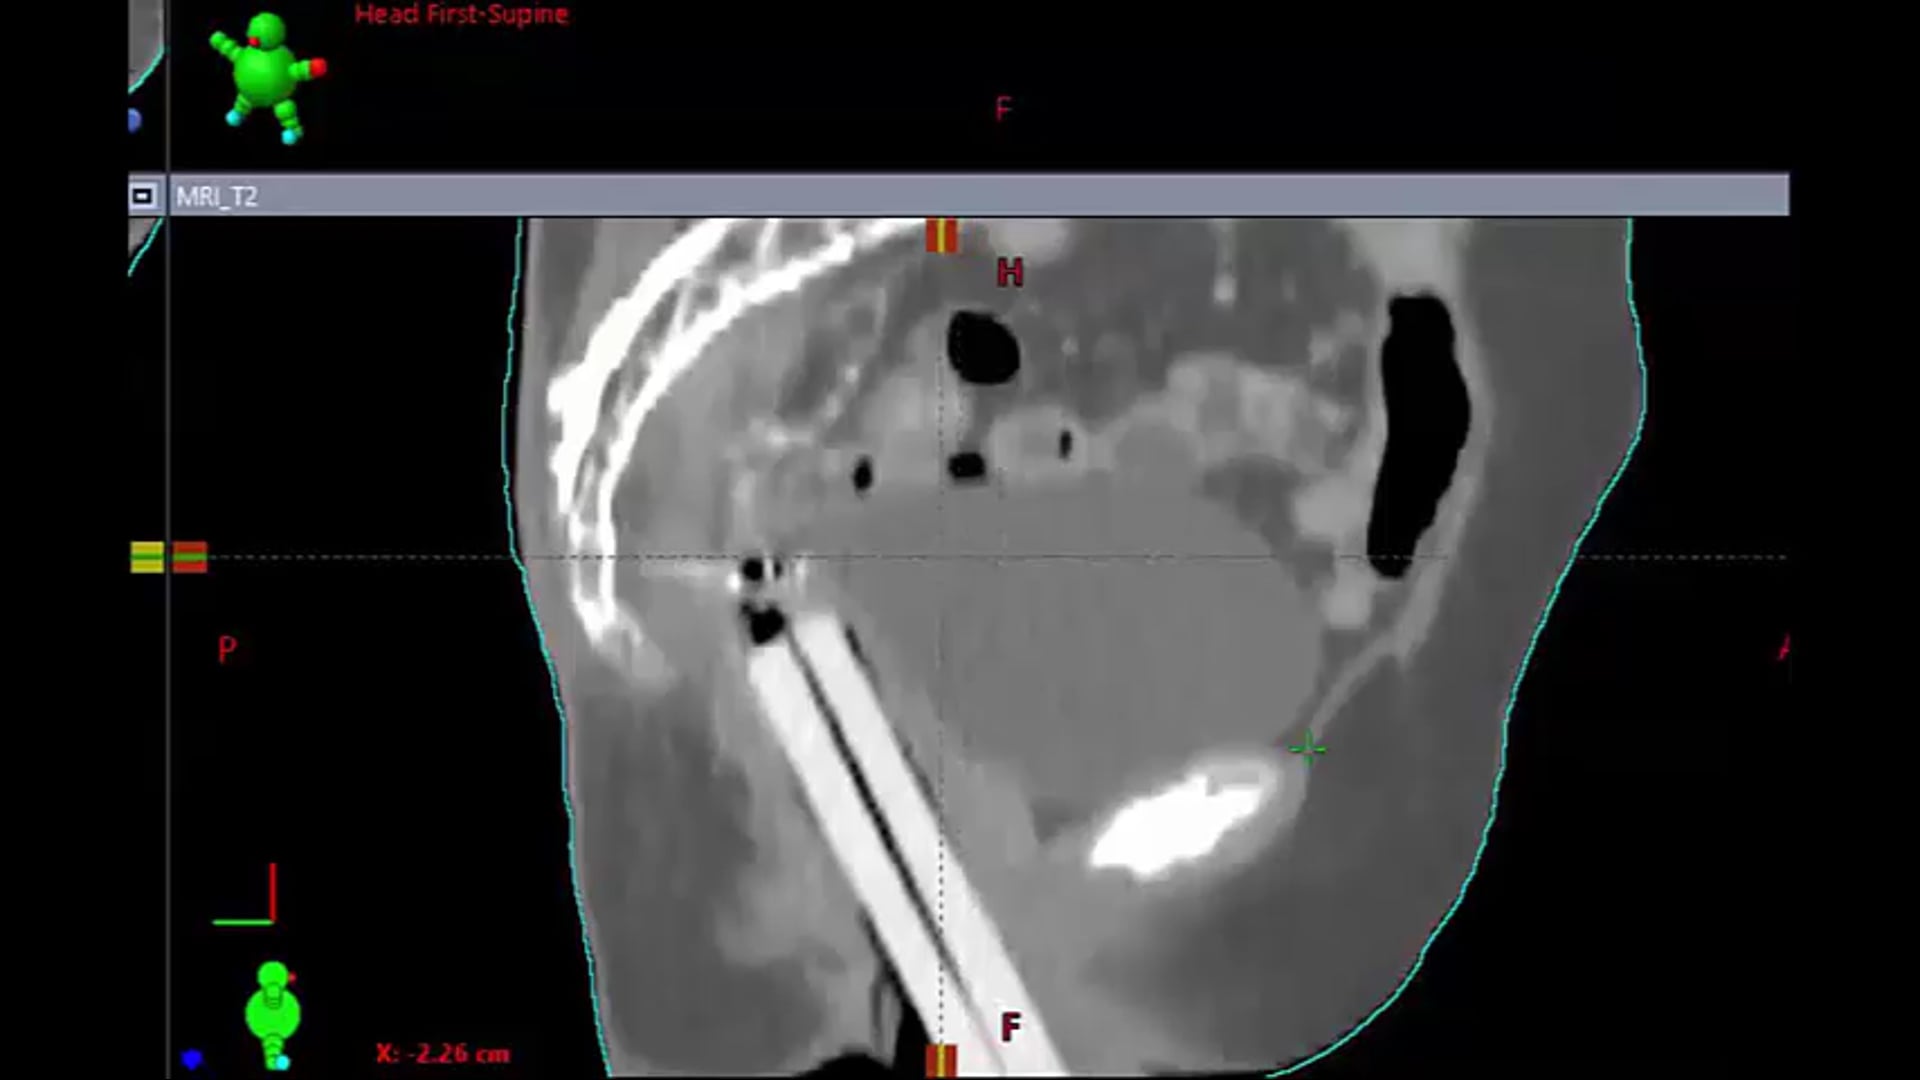

endometrial adenocarcinoma, para-aortic nodes, PET CT, diabetes, charcot arthropathy, groin nodes, pelvis, negative cervical margins, cisplatin, small bowel, Harkenrider, contouring, MRI, tumor, vaginal bleeding, relapse, persistence, cylinder, dose distribution, dosimetry, brachytherapy, fractio...

squamous cell carcinoma, dysplasia, PET, SIB, brachytherapy, endocervical, MRI, nodal location, inguinofemoral, right external iliac, CTV, deescalation, dosimetry, sigmoid, hysterectomy, concurrent chemoradiation, stenotic cervix, abdominal infection, external planning, avoid structure, antibioti...

chemotherapy, radiation therapy, sandwich regimen, brachytherapy, well differentiated endometrioid adenocarcinoma, neoadjuvant chemotherapy, small bowel, dilation, dosimetry, gross disease dose, MRI, cirrhosis, external beam radiation, Rotte Y applicator, CT scan, dual tandem, 3-D printing, endom...